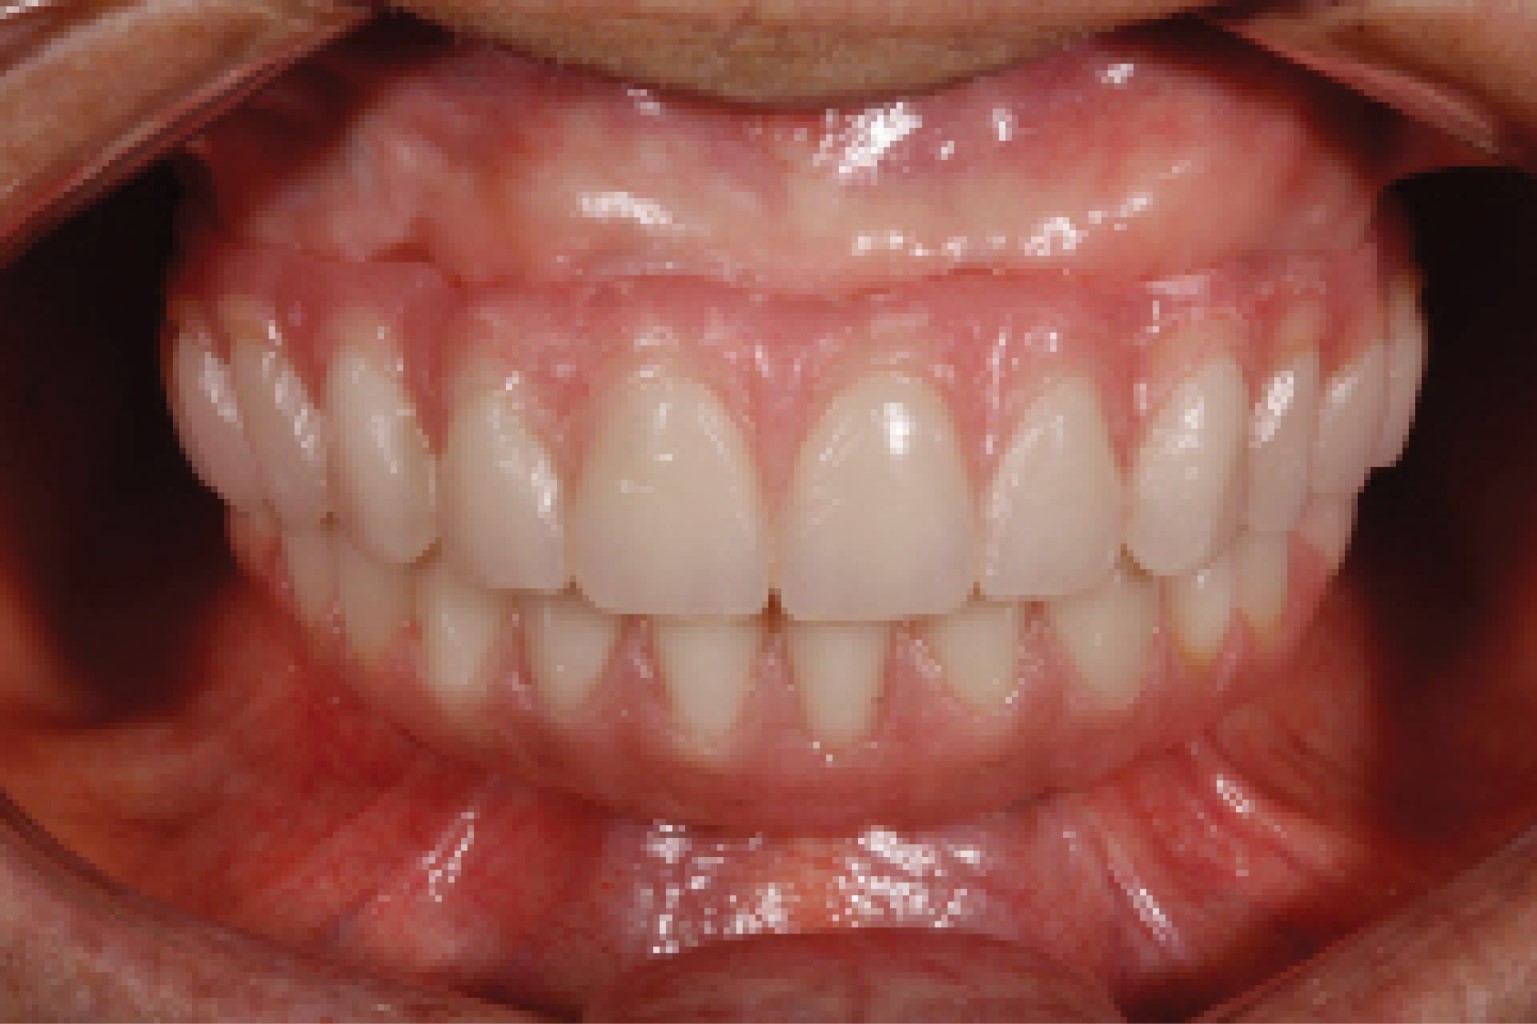

Hoy en día el uso de implantes dentales constituye el estándar de oro en la rehabilitación protésica de pacientes edéntulos. Especialmente en los pacientes totalmente edéntulos, es importante una correcta colocación tridimensional de los implantes para garantizar unos resultados funcionales y estéticos adecuados. En los últimos años, el uso de sistemas quirúrgicos guiados por ordenador ha permitido la colocación de implantes con una precisión casi exacta del resultado quirúrgico/protésico final. El presente caso describe un enfoque sin colgajo para la rehabilitación completa de pacientes edéntulos mediante el protocolo de doble escaneo para la planificación virtual de la colocación de implantes y el diseño de la guía quirúrgica para la rehabilitación de implantes en pacientes totalmente edéntulos. La cirugía guiada es actualmente una alternativa que permite, en los casos adecuados, realizar un abordaje sin colgajo, lo que reduce las molestias del paciente, el tiempo quirúrgico y mejora la precisión de la colocación del implante al reducir el error del operador.

Figura 2